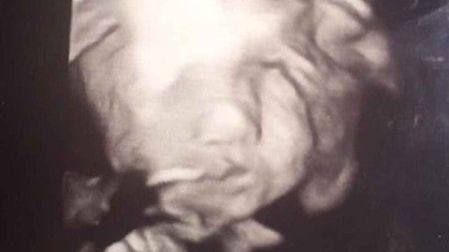

Iyanna Carrington, una mujer de 17 años de edad originaria de Richmond Virginia, se realizó una ecografía y descubrió una aterradora imagen en su interior que ‘parece diablo’.

En la ecografía aparece su hija mirándola con una sonrisa sumamente aterradora y con los ojos muy abiertos.

Médicos comentaron que la postura del bebé también es muy rara pues no suelen colocarse frente a la cámara durante el ultrasonido.

Pese a la foto, los médicos le aseguraron que su bebé cuenta con una excelente salud.